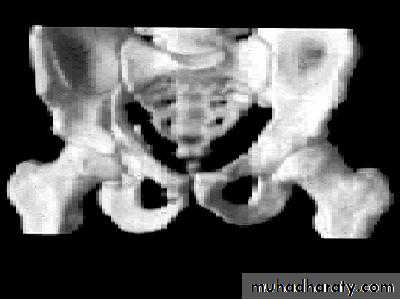

HIP DISLOCATION

anatomy

Injuries of the hip and femurThe magnitude of force needed to dislocate the hip joint particularly well-contained by virtue of its bony and soft-tissue anatomy.

is so great that the dislocation is often associated with fractures - either around the joint or elsewhere in the same limb.

Hip dislocations are classified according to

the direction

of the femoral head displacement:

Traumatic Dislocations of the hip.

Posterior.Anterior.

Central.

Posterior dislocation: